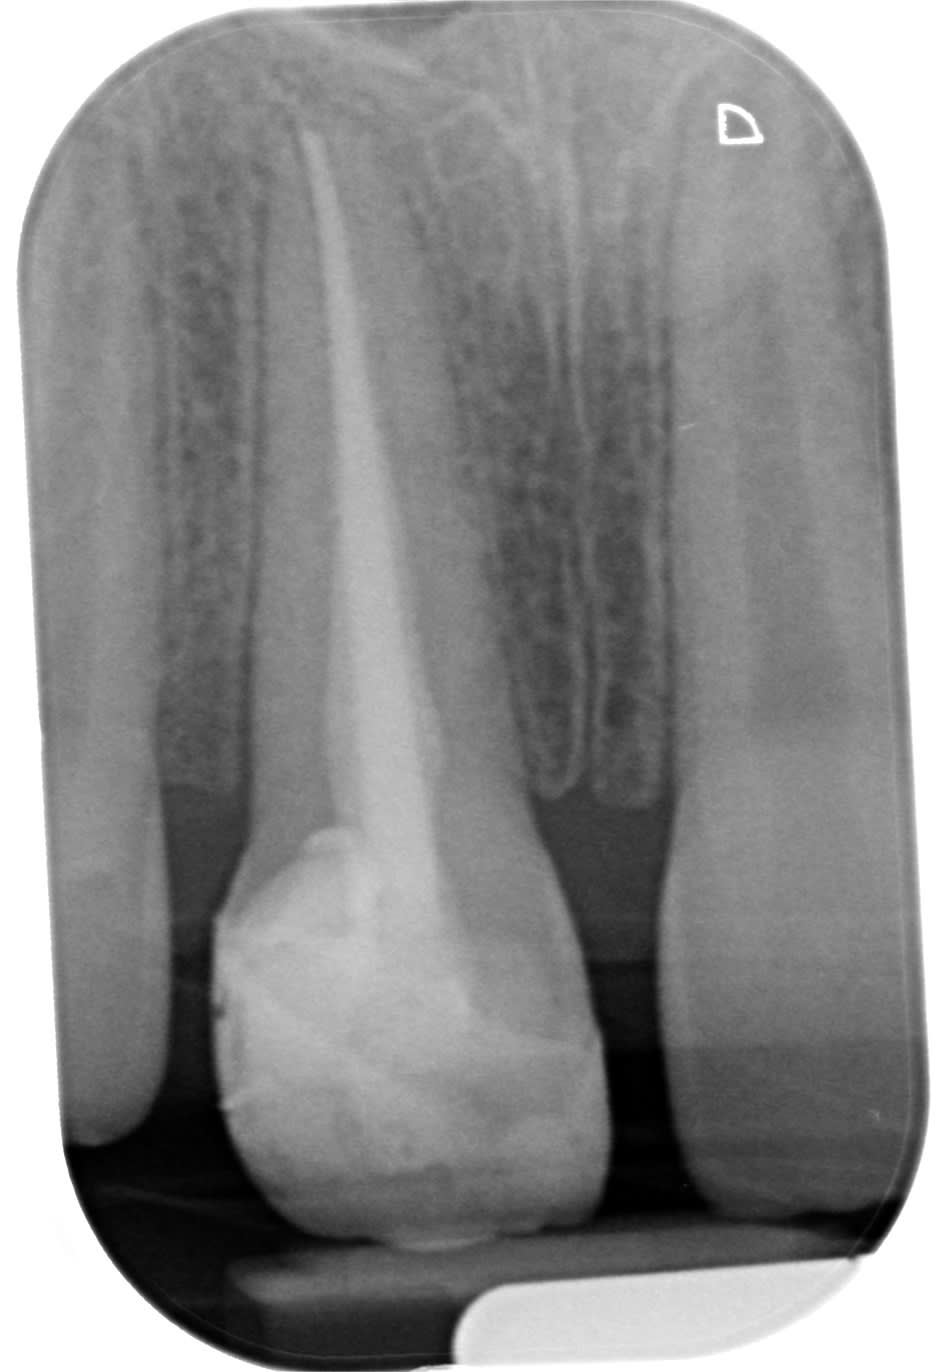

Poser un pangen et coter un comblement c'est du vol. Selon mon CD conseil coter une photo pour justifier ton acte et ou enregistrer tes rapports occlusaux est justifié. bien sur si tu fais un compo de merde dans la salive prendre une photo NR c'est du vol. je pense pas voler mes patients. Les parents du gosse dont je joint le cas n'ont trouvé que je suis un voleur ( malgré les 400 NR) alors qu'ils attaquent le confrère au tarif conventionné.

Difficile a voir sur la radio ; tu as mis un pivot?,